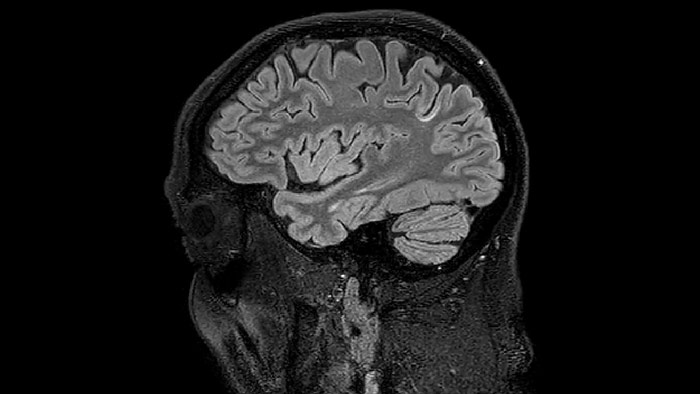

He says the accelerated scanning is achieved via the use of Compressed SENSE and MultiBand SENSE. “We can use Compressed SENSE acceleration factors of about 10 on a 3D FLAIR for instance, which is quite remarkable compared with what we saw with the Achieva. With 3D FLAIR, we can push the spatial resolution to 0.3 cubic mm and it works. Previously, our 3D FLAIR scans lasted about 8 minutes, but now with Elition they are five minutes. The SNR is also visibly better. Our SWI and QSM scans look fantastic. Also, since a lot of neuroimaging is EPI based, using the MultiBand SENSE technique can increase temporal resolution and make it possible to run complicated DTI scans relatively quickly.”

Sagittal 3D FLAIR with 0.3 mm3 voxel volume acquired in 5:12 min. using Compressed SENSE showing a (juxta)cortical MS lesion.

QSM based on a Compressed SENSE multi-echo SWI.